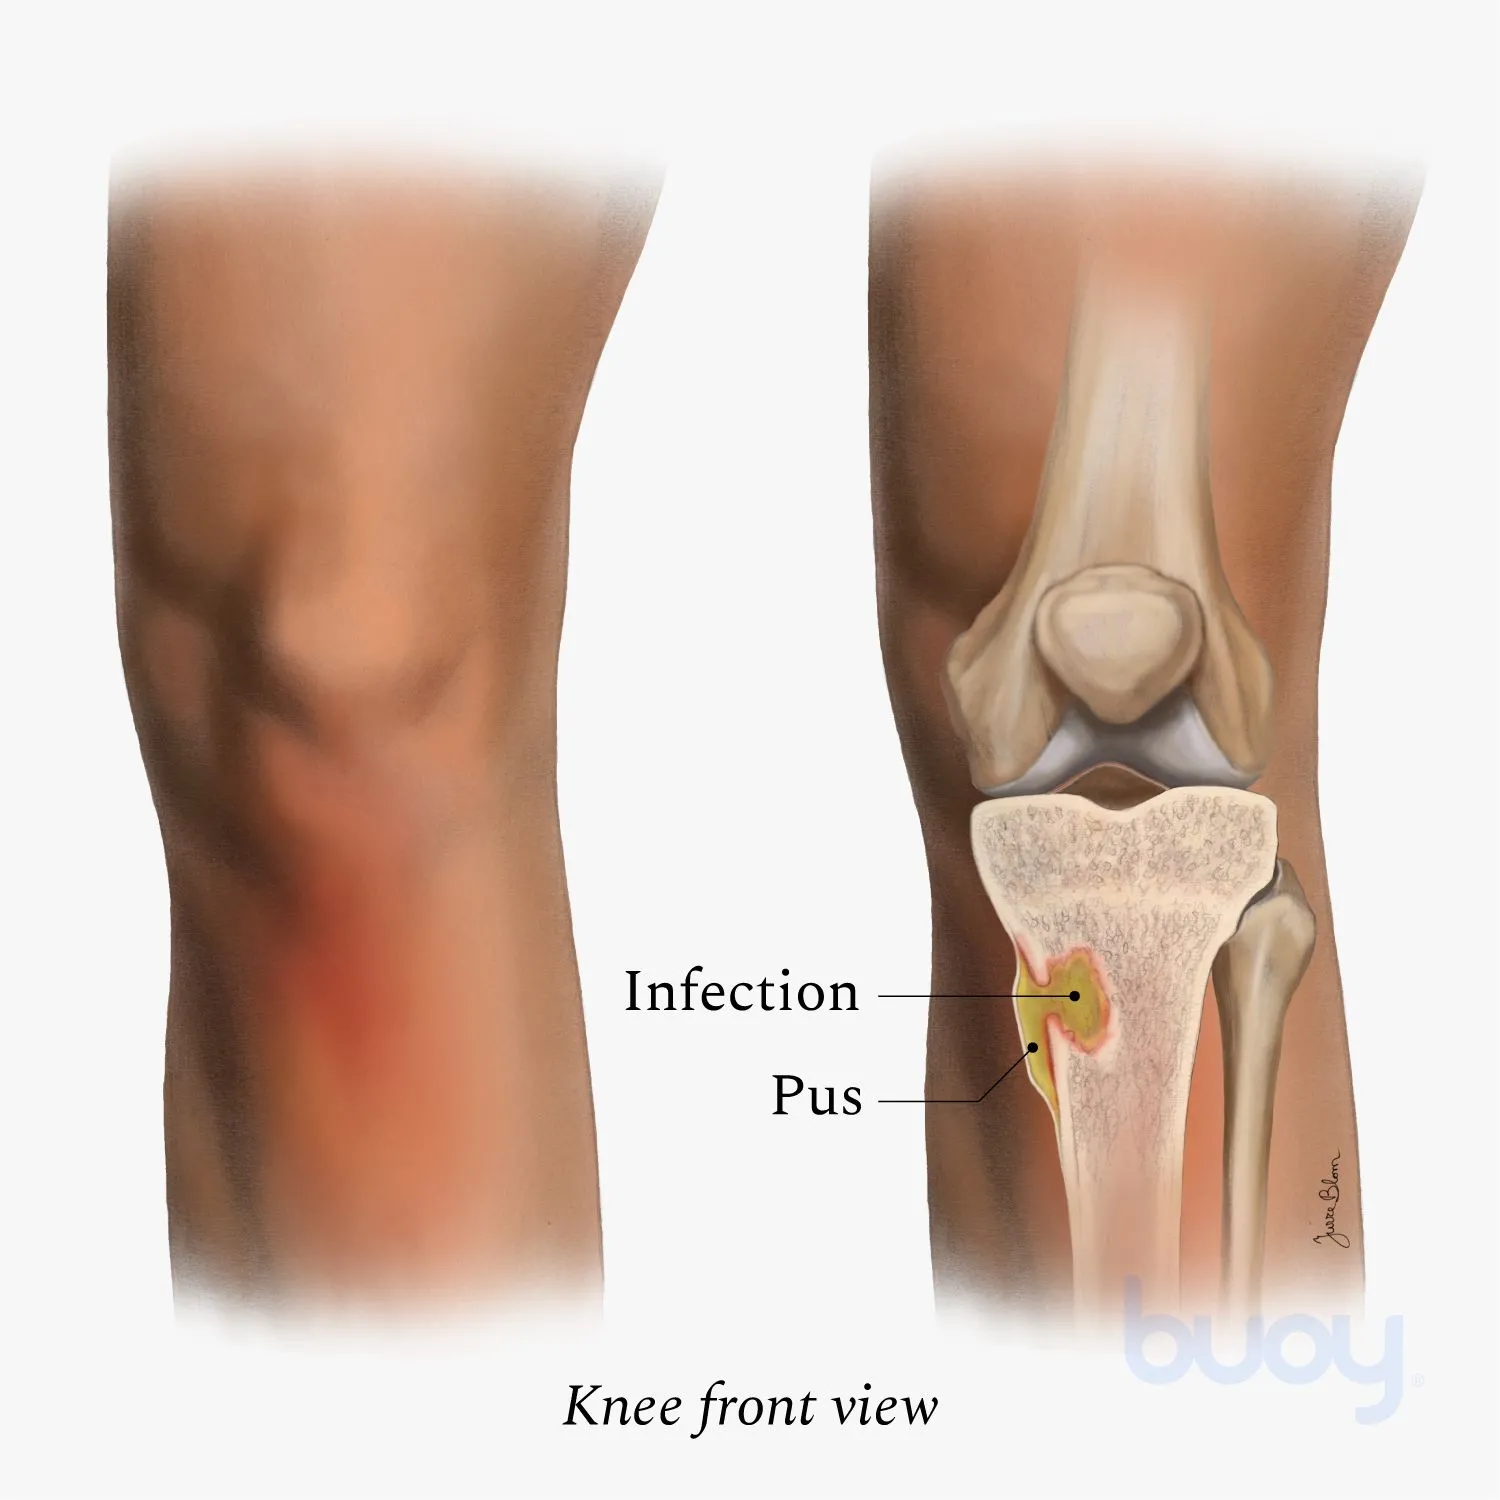

What causes bone infections?

Bone infections typically result from bacterial invasion through open wounds, surgical sites, or bloodstream spread from other infected areas in the body. Common risk factors include diabetes, compromised immune system, and previous bone trauma.

How serious is a bone infection?

Bone infections are serious medical conditions that can lead to permanent bone damage, chronic pain, and life-threatening complications if left untreated. Early diagnosis and treatment are crucial for optimal outcomes.